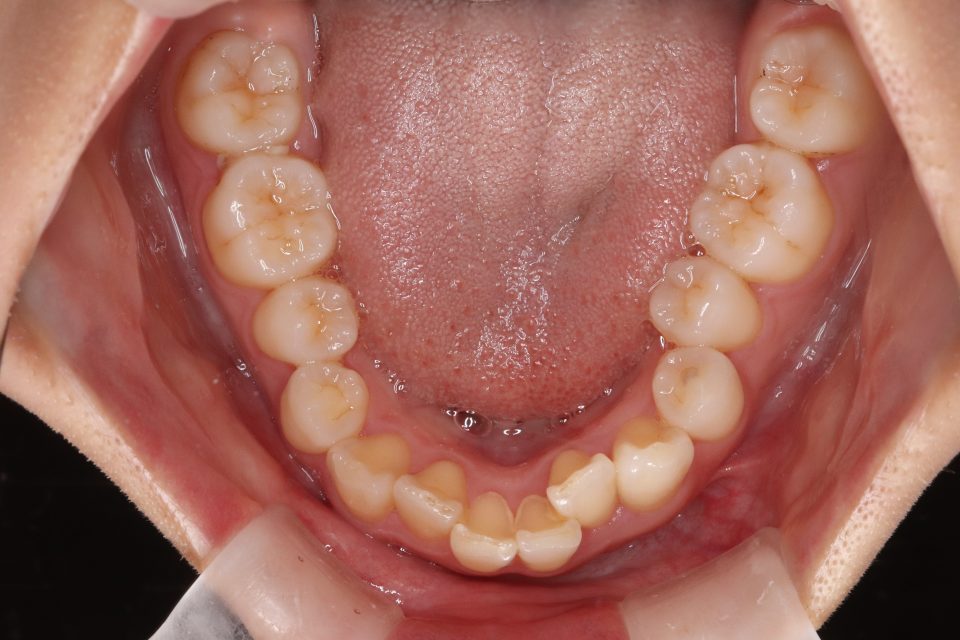

矯正治療前

歯並びのガタガタと出っ歯気になり矯正治療を始めました。

左上4番目の歯を抜歯して、マウスピース型の矯正治療装置を使用し、歯のやすり掛け(IPR)を行いました。